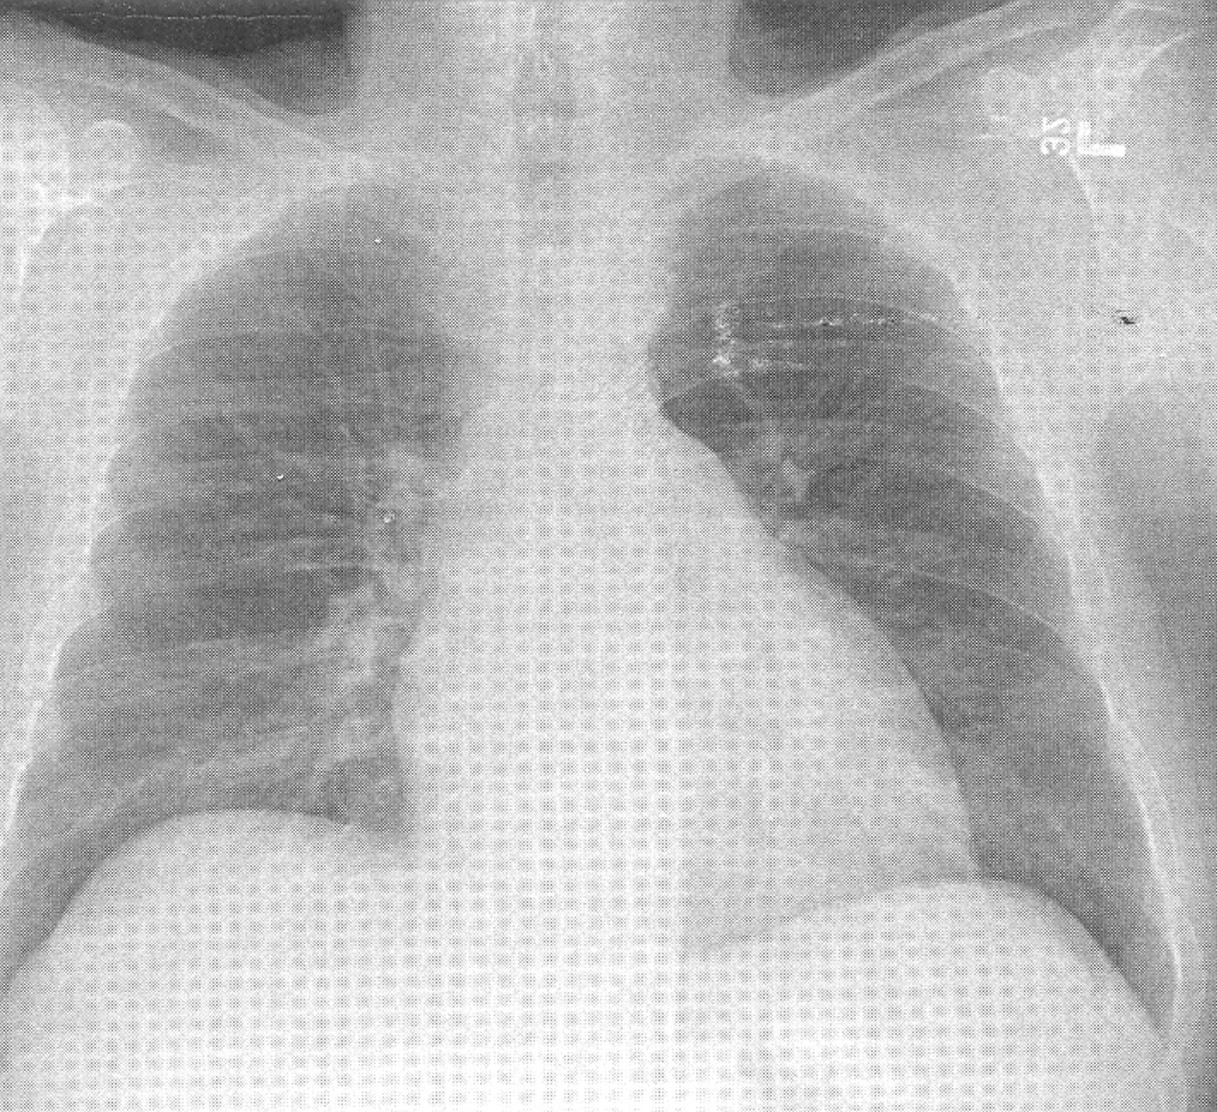

The patient's chest x-ray shows evidence of chronic pulmonary hypertension (cor pulmonale).

Note the prominant main pulmonary artery segment and the rounded left cardiac border

(an enlarged right ventricle). The physical findings of a loud pulmonary artery closure

(S2P), retrosternal dullness, and a parasternal tap are all characteristic of pulmonary

hypertension and right ventricular hypertrophy.